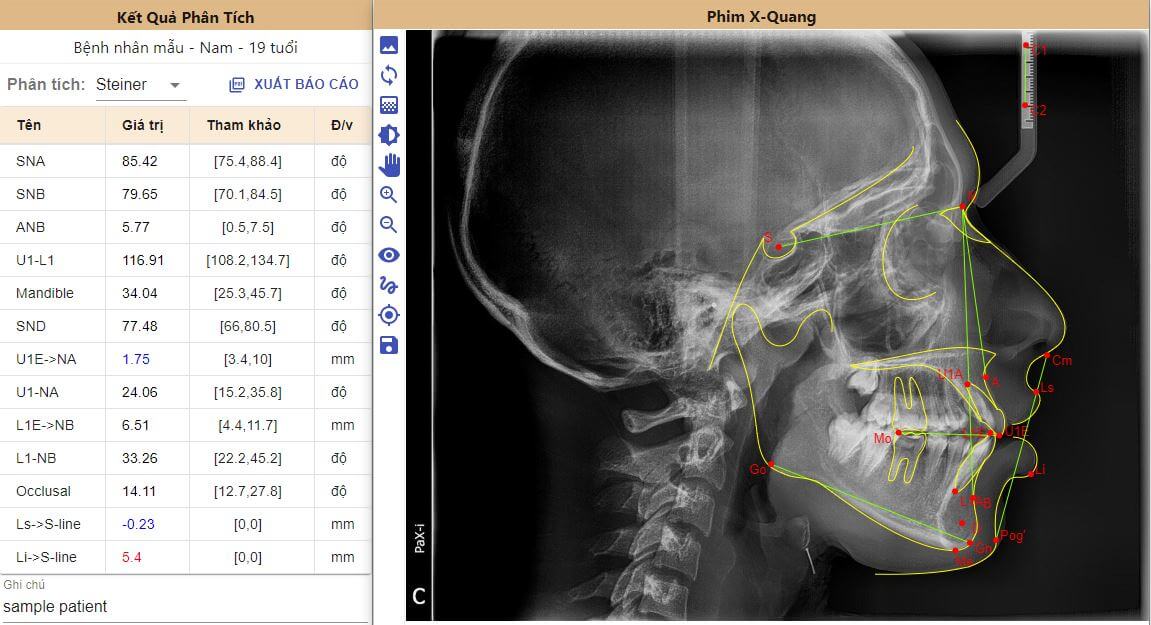

2. Phim sọ nghiêng Cephalometric

Phim này được bác sĩ sử dụng để phân tích các góc độ về răng, xương, các chỉ số mô mềm. Dựa trên các thông số này mà bác sĩ có thể xác định nguyên nhân hô, móm là do xương hay do răng, từ đó đưa ra được phương pháp điều trị hợp lý.